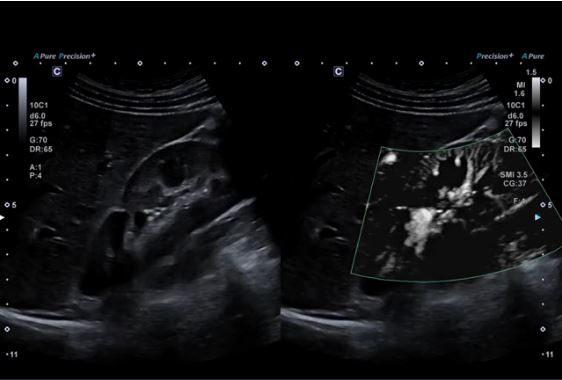

Технологія візуалізації мікропотоків (SMI) відображає кровотоки низької швидкості у нирці.

Висока частота кадрів підтримується за допомогою SMI відображаючи перфузію в нирці при використанні мікроконвексного датчика.

Конвексний датчик PVU-574BT (10C1)

Високочастотний монокристалічний конвексний датчик забезпечує високу просторову роздільну здатність і проникнення для підвищення клінічної впевненості в акушерських, неонатальних та інших дослідженнях.